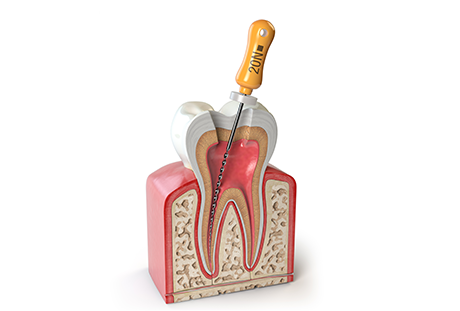

むし歯菌に感染した神経を除去し、内部を洗浄・消毒して薬剤を詰めることで歯を残す「根管治療」を行います。

根管治療は多くのステップをじっくり時間をかけて行うため治療を続けていただく必要があります。治療を中断してしまうと計画通りに治療が進められなくなってしまうため根気よく通院するようにしましょう。